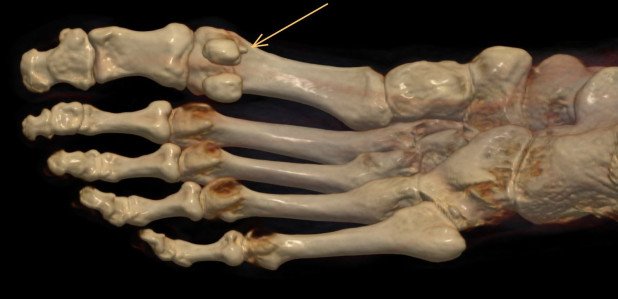

Plantarer Osteophyt

3D-Darstellung des Fusses mit Überbein

Solche Überbeine werden in der Fachsprache als Osteophyten bezeichnet und bilden sich bei beginnenden Arthrosen. Dass diese in eine schmerzhafte Richtung nach unten wachsen ist sehr selten.